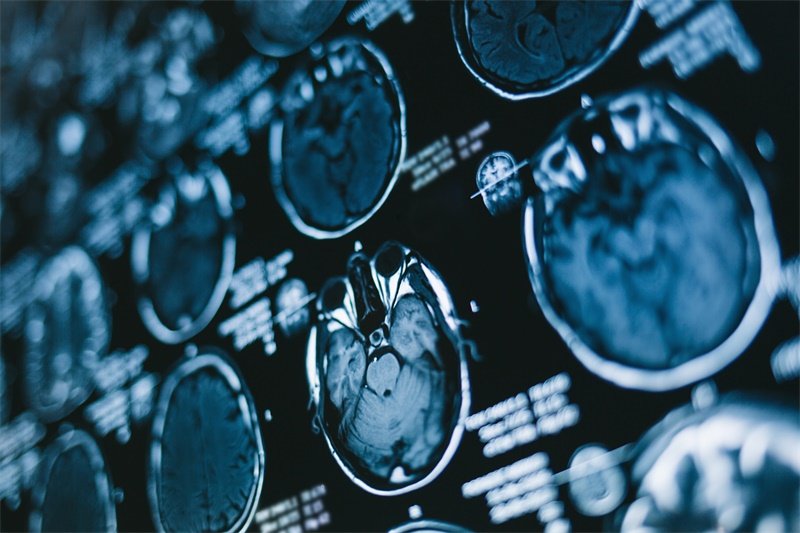

如何诊断垂体占位伴出血

影像学检查

影像学检查是诊断垂体占位病变的首要工具。常见的检查方法包括磁共振成像(MRI)和计算机断层扫描(CT)。这两种影像学技术能够清晰地显示垂体肿瘤的大小、位置及其与周围组织的关系。

此外,增强扫描可以发现肿瘤内的出血和水肿,这对于医生判断病变性质和制定治疗方案非常重要。